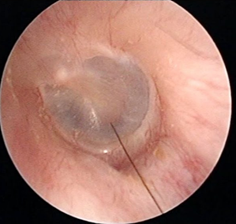

另一方面,如果小概率情况真的发生在你身上,因耳垢栓塞引发听力障碍、耳痛、耳鸣、耳堵塞感等症状,那确实是得掏。

但不是让我们自己掏,而是要去医院耳鼻喉科请医生做专业的诊断,再用专业的器材小心地取出来,必要时还需要配合其它治疗。